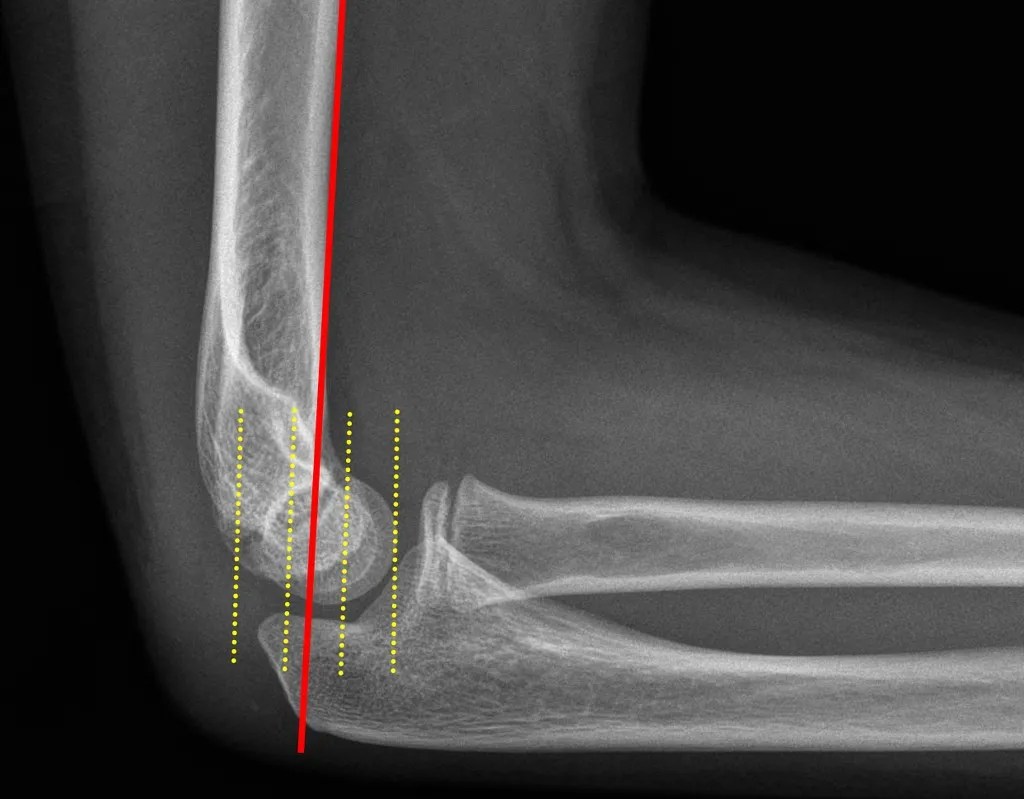

From dontforgetthebubbles.com

Olecranon fractures Types Of Elbow Fractures In Adults An olecranon fracture usually causes sudden, intense pain and can prevent you from moving your elbow. Type i and ii fractures are usually treated without surgery, while type iii fractures typically need surgery. Elbow fractures and dislocations are commonly seen in the acute care setting. Radial head and neck fractures (see figure 2) the radial head and neck, which are. Types Of Elbow Fractures In Adults.